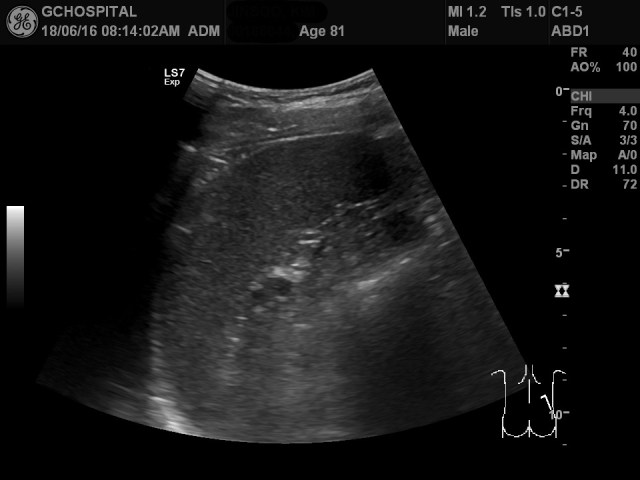

그런데, 엎드린 상태에서 오른쪽 옆구리를 확인하니 전형적인 비장의 형태가 확인되었습니다.